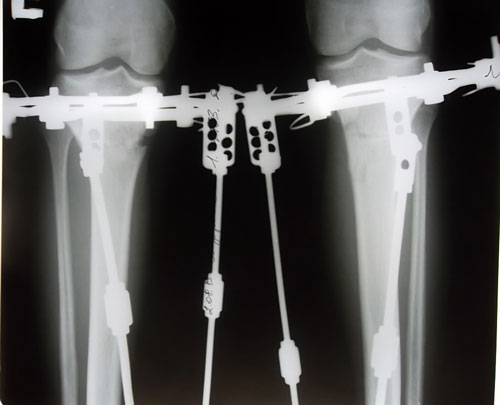

Рентгеновские снимки в 2 месяца.

Вложения

SAM_6041.JPG

SAM_6037.JPG